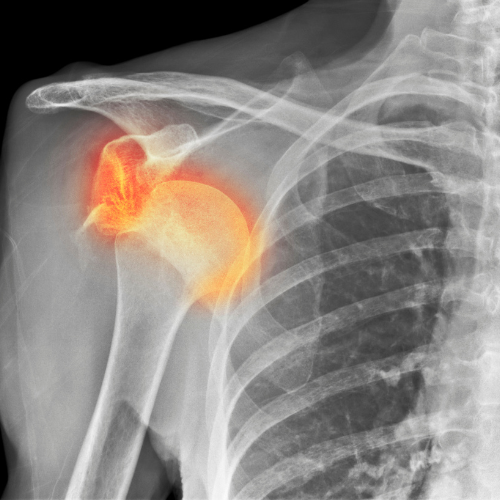

বার বার কাঁধের জোড়া ছুটে যাওয়া